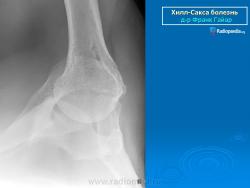

На рентгенограмме плечевого сустава определяется умеренный остеопороз головки плечевой кости. Иногда на ее задненаружной поверхности позади вершины большого бугорка выявляется вдавленный дефект (повреждение Хилл-Сакса). Дефект четко виден на рентгенограмме в аксиальной проекции. Аналогичный, но менее выраженный дефект может быть выявлен в зоне передненаружного края суставной впадины лопатки. Также в диагностике причин привычного вывиха плеча помогает МРТ исследование.

рентгенограмма плечевого сустава. Повреждение Хилл-Сакса и сопутствующий кальциноз сухожилий вращательной манжеты